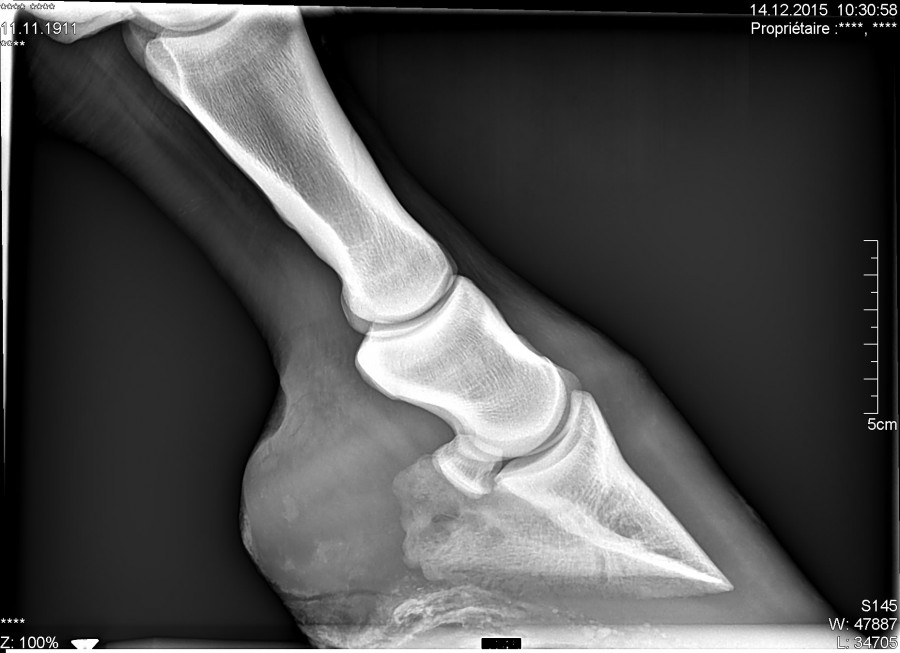

Pour ceux que ça intéresse, les radios :

Alors le verdict .... Une grosse fourmilière qui remontait très haut et qui décollait la paroie, ils ont charcuté tout ça, elle a un gros trou dans la paroie, ça va nécessiter des soins et du temps pour que ça repousse, mais au moins ce n'est pas un problème plus grave et chronique !

Il sonde le pied, qui est clairement la cause de la boiterie selon lui, et décide de faire une radio, malgré cela il n'arrive pas à localiser l'abcès, mais détecte, une petite déformation de la 3 ème phalange, pile à l'endroit ou l'espèce de bosse s'est formée dans la boîte cornée.